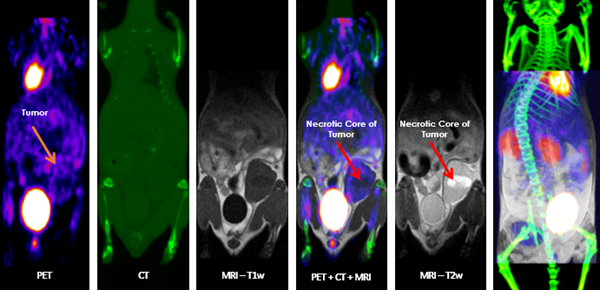

Multimodal Imaging: Multimodal imaging combines the strength of MRI with other imaging modalities such as PET and CT. PET provides information on the spatial distribution of molecular signal of interest. In this case MRI confirmed that the absence of tracer uptake in the center of the images was due to the presence of a necrotic core, which appears hyperintense on T2-weighted MRI. Image Credit: Scintica Instrumentation Inc

Multimodal imaging

According to current preclinical imaging trends, multimodal imaging can provide synergistic information on a particular disease model or response to a target compound, and it should be considered in all studies wherever feasible. The SimPET insert can be integrated with the M-Series to enable simultaneous PET/MRI.

Alternatively, the animal can be transported to different imaging modalities using a multimodal imaging cassette to fit inside the MRI coil on the M-Series. These images can be co-registered using third-party software like VivoQuant.

Multimodal imaging combines the strength of MRI with other imaging modalities, such as PET and CT. PET provides information on the spatial distribution of molecular signal of interest. In this case MRI confirmed that the absence of tracer uptake in the center of the images was due to the presence of a necrotic core, which appears hyperintense on T2-weighted MR. Image Credit: Scintica Instrumentation Inc